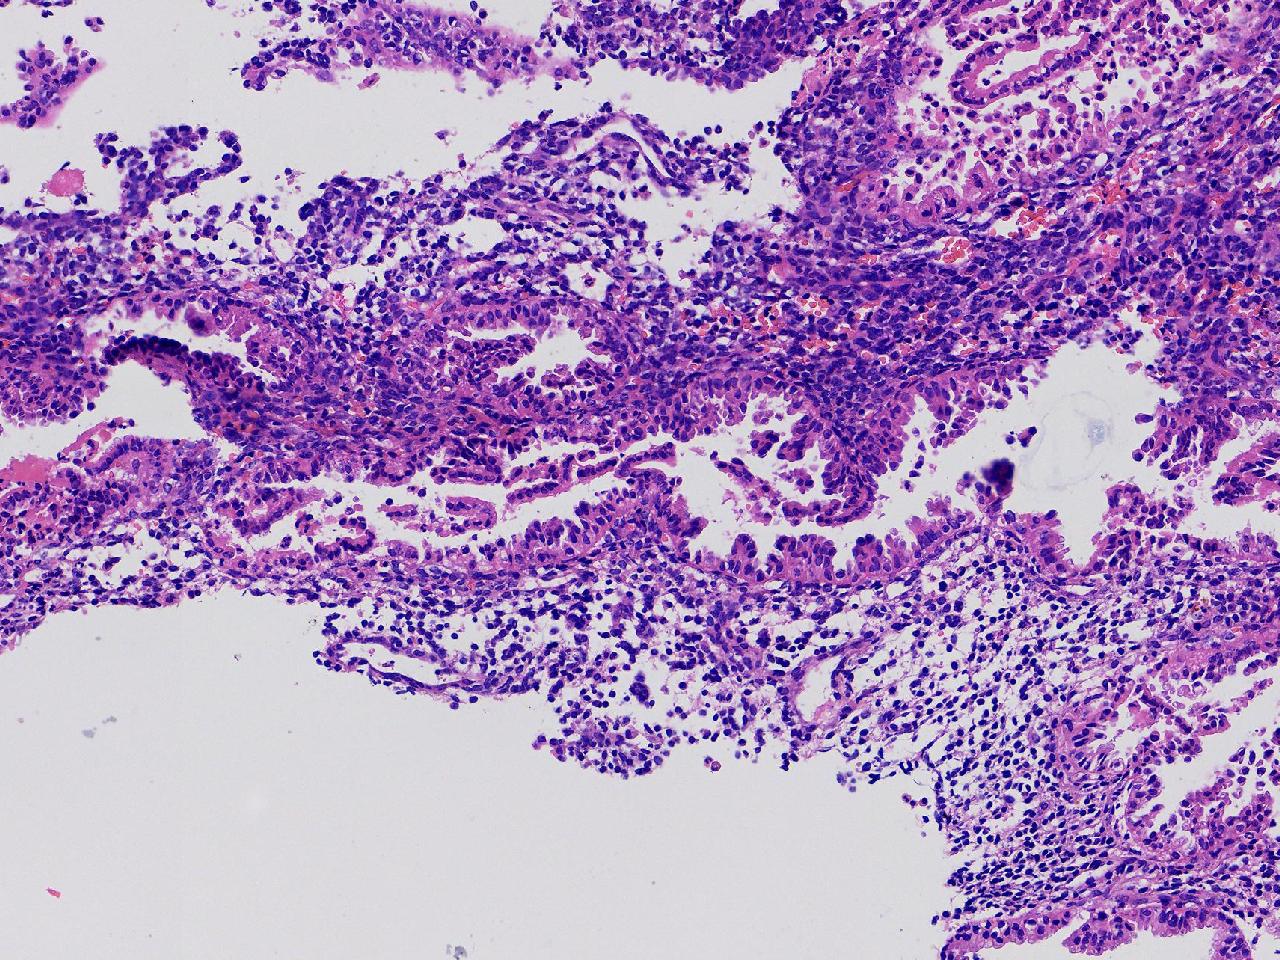

性别

女

年龄

45岁

临床诊断

阴道不规则出血20余天,

一般病史

彩超示:宫腔内见约41X11毫米的不均质回声区。宫腔镜示:宫腔形态正常,内膜粉红,不规则增厚。

标本名称

子宫内膜

大体所见

灰粉色不整形软组织多块,1.5X1X0.6厘米。

分泌反应子宫内膜,伴有出血。

晚泌期及月经早期改变,局部呈啫酸性乳头状化生改变。